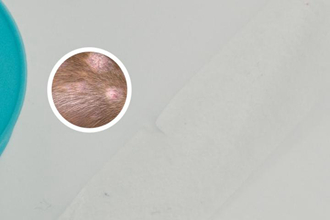

烏魯木齊窄波uvb紫外線光療的療程并不是一概而論,無法給出確切的“多久能好”的答案。白癜風(fēng)的治療是一個(gè)漫長(zhǎng)而復(fù)雜的過程,其治療的效果與多種因素息息相關(guān),包括白斑的面積、病程長(zhǎng)短、患者的個(gè)體差異、治療方案的制定以及治療的依從性等。窄波uvb光療作為一種輔助治療手段,其治療的效果的顯現(xiàn)也因人而異,有的患者可能在數(shù)周內(nèi)看到顯然改善,而有的患者則需要更長(zhǎng)時(shí)間的治療。我們必須注意,治療時(shí)間并不是衡量治療的效果的標(biāo)準(zhǔn),關(guān)鍵在于根據(jù)患者的具體情況制定個(gè)性化的治療方案,并堅(jiān)持規(guī)范治療。

影響烏魯木齊窄波uvb紫外線光療療程的因素是多方面的。白斑的面積和部位至關(guān)重要。面積較小、位于暴露部位的白斑通常比面積較大、位于隱蔽部位的白斑更容易治療。白癜風(fēng)的病程長(zhǎng)短也影響治療的效果。病程較短的白斑通常比病程較長(zhǎng)的白斑更容易治療。患者的個(gè)體差異,例如年齡、免疫狀況、內(nèi)分泌狀況等,都會(huì)影響治療的效果。醫(yī)生的經(jīng)驗(yàn)和治療方案的合理性也是決定療程的關(guān)鍵因素,合理的治療方案需要結(jié)合患者的具體情況,制定個(gè)性化治療方案,而經(jīng)驗(yàn)豐富的醫(yī)生更能夠根據(jù)患者的病情變化調(diào)整治療方案。

在烏魯木齊,窄波uvb光療通常每周進(jìn)行2-3次照射,每次照射時(shí)間和劑量根據(jù)患者的皮膚反應(yīng)進(jìn)行調(diào)整,醫(yī)生會(huì)根據(jù)患者的具體情況制定詳細(xì)的治療方案。一般情況下,需要4-8周左右才能觀察到治療的效果,但這只是一個(gè)大概的時(shí)間范圍,實(shí)際情況因人而異。在治療過程中,醫(yī)生會(huì)密切關(guān)注患者的皮膚反應(yīng),并根據(jù)需要調(diào)整治療方案?;颊咭残枰e極配合醫(yī)生的治療,按時(shí)復(fù)診,及時(shí)反饋治療中遇到的問題。